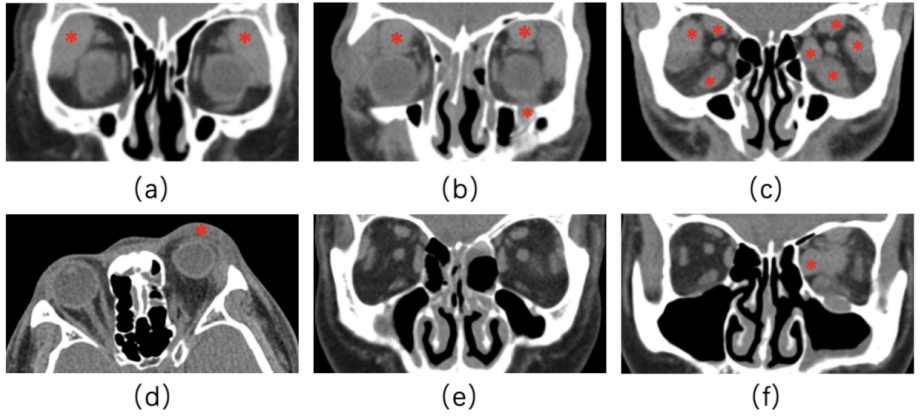

眼眶影像学特征性表现:本组29例患者眼眶CT中,泪腺均受累(100%,22例双侧泪腺均受累,7例单侧泪腺受累),17例(58.62%)患者眼外肌受累,5例(17.24%)患者三叉神经分支受累(4例眶下神经受累,3例额神经受累,2例眶下神经与额神经同时受累), 24例(82.76%)患者眼睑组织受累(19例双侧眼睑同时受累,5例单侧眼睑受累),15例(51.72%)患者鼻黏膜受累,出现类炎症反应,2例(6.90%)患者合并眶内其他增生性病变。见图3。

图 4 IgG4-ROD的典型CT表现

Figure 4 Typical CT image of IgG4-ROD

3.3 IgG4-ROD影像学特征

Sogabe等[42]总结的IgG4-ROD好发部位为泪腺(87.7%)、三叉神经分支(38.5%)、眼外肌(24.6%)、眶脂肪(23.1%)、眼睑(12.3%)。本组研究发现,IgG4-ROD患者泪腺受累最多(100%),此外依次为眼睑(82.76%)、眼外肌(58.62%)、鼻黏膜(51.72%)、三叉神经分支(17.24%)受累,6.90%患者合并眶内其他增生性病变。本研究患者主要表现为泪腺受累,与文献结果一致。本研究中患者多部位受累的比例高于既往文献报道,考虑可能是由于患者就诊于我院时疾病已处于较严重阶段。少数情况会发生眶内其他软组织增生性病变,但并非罕见,提示临床发现眶内不明来源的占位时,也要考虑到IgG4-ROD的可能性。3.4 血清IgG4水平升高与影像表现的相关性